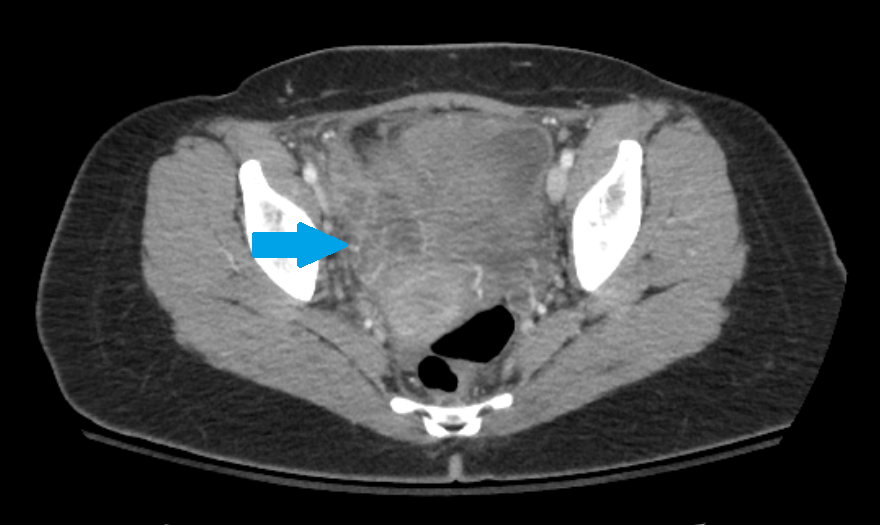

A 43 yo F presents to the ED with RLQ abdominal pain x 3 weeks. She reports 1 day of fever and chills. Abdominal/pelvic exam is significant for RLQ and suprapubic tenderness, as well as R adnexal tenderness and fullness. A CT scan is obtained. What's the diagnosis? (scroll down for answer)

Answer: Right tubo-ovarian abscess

- CT findings (as shown above) include tubular and cystic fluid collections with rim enhancement consistent with abscess formation